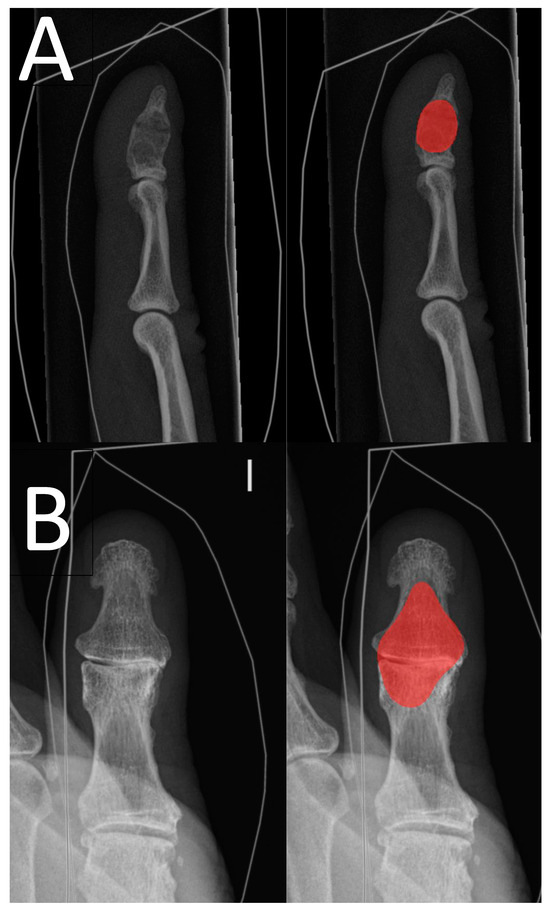

The inter-rater reliability of the clinical experts was good, with a value of 0.96. The results are presented in more detail in Table 2. Clinical expert 2 drew an enchondroma in healthy bone tissue in adjunct to the correct drawing in one enchondroma radiograph. Table 3 shows the confusion matrix for the DL model’s enchondroma detection. In Figure 3, correct and incorrect predictions of the DL model are shown.

Figure 3. Examples of the DL model’s predictions. Image pair (A) shows a distal phalange true-positive prediction (red area) of an enchondroma with a pathological horizontal fracture, and image pair (B) shows a false-positive prediction (red area) of thumb interphalangeal joint area with osteoarthrosis.